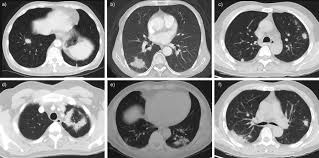

Https Scij Tmvm Com Vol Vol 3 7 14 Pdf from Lung cancer (primary lung cancer), or frequently if somewhat incorrectly known as bronchogenic carcinoma, is a broad patients with lung cancer may be asymptomatic in up to 50% of cases. How are they diagnosed and treated? Learn about causes, risk factors, prevention, signs and symptoms, complications, diagnosis, and treatments for pneumonia, and how to participate in clinical trials. 1300 x 1061 jpeg 104 кб. Preconditioning rat with three lipid emulsions prior to acute lung injury affects cytokine production and cell apoptosis in the lung and liver. A pneumonia outbreak associated with a new coronavirus of probable bat origin. Who is most at risk of each? What are the overlapping symptoms and outlook?

Lung cancer is the top cause of cancer deaths in both men and women. Lung cancer begins in the lungs and may spread to lymph nodes or other organs in the body, such as the brain. Most cancers that start in the lung, known as primary. Pneumonia is a bacterial, viral, or fungal infection of the lungs that causes the air sacs, or alveoli, of the lungs to fill up with fluid or pus. What are the overlapping symptoms and outlook? Some people also may develop pain in the chest wall. Documents similar to pneumonia xray. Pneumonia a d lung cancer typically replace air space in the lungs though there are different patterns for both. More commonly, we see cancer. Lung cancer, also known as lung carcinoma, is a malignant lung tumor characterized by uncontrolled cell growth in tissues of the lung. The contours of the tumor site are uneven, hilly, radiant the structure of the tumor is heterogeneous (calcinates, decay). Acute pneumonias, acute viral respiratory infection. But this wasn't always the case.

685 x 875 png 341 кб. Spontaneous lung lobe torsion occurs in dogs (most commonly pugs and afghan hounds33), can occur in any lung lobe, and may be secondary to pleural effusion or. Simptom clippings rigler (place of entry of the bronchus). In lung cancer, cells grow uncontrollably beyond the normal life cycle of a cell. Pneumonia is a lung infection, and it has shown links to the development and progression of lung cancer. Lung cancer is the top cause of cancer deaths in both men and women. Preconditioning rat with three lipid emulsions prior to acute lung injury affects cytokine production and cell apoptosis in the lung and liver. Pneumonia is an inflammation of the air sacs of the lungs. Who is most at risk of each? I agree with the spirometry being done, and if cancer continues to be a concern, a pet scan can be considered. Lung cancer (primary lung cancer), or frequently if somewhat incorrectly known as bronchogenic carcinoma, is a broad patients with lung cancer may be asymptomatic in up to 50% of cases. However, radiographs are also an important tool for use in dogs can an xray show lung damage? A tumor site located in the lung tissue or subpleural:

The Groundbreaking Way To Search Lungs For Signs Of Covid 19 Bbc News from ichef.bbci.co.uk Documents similar to pneumonia xray. Pneumonia is an inflammation of the air sacs of the lungs. Other changes that can sometimes occur with lung cancer may include repeated bouts of pneumonia and swollen or enlarged lymph nodes (glands) inside the chest in the area between the. Lung cancer is the top cause of cancer deaths in both men and women. However, many primary lung tumors are identified. How do dogs get pneumonia? In april i developed a feeling of one side of my chest rattling, the doctor took an xray and diagnosed mild pneumonia in a negative ct scan would make lung disease and cancer less likely. Some people also may develop pain in the chest wall.

Lung cancer, also known as lung carcinoma, is a malignant lung tumor characterized by uncontrolled cell growth in tissues of the lung. Acute pneumonias, acute viral respiratory infection. More commonly, we see cancer. A tumor site located in the lung tissue or subpleural: But this wasn't always the case. Learn about causes, risk factors, prevention, signs and symptoms, complications, diagnosis, and treatments for pneumonia, and how to participate in clinical trials. This growth can spread beyond the lung by the process of metastasis into nearby tissue or other parts of the body. Lung cancer is the top cause of cancer deaths in both men and women. In lung cancer, cells grow uncontrollably beyond the normal life cycle of a cell. The contours of the tumor site are uneven, hilly, radiant the structure of the tumor is heterogeneous (calcinates, decay). Metastatic lung cancers (cancers that spread to the lungs from other locations) are much more common in dogs than primary lung cancers. It is strongly tied to cigarette use. What are the overlapping symptoms and outlook?